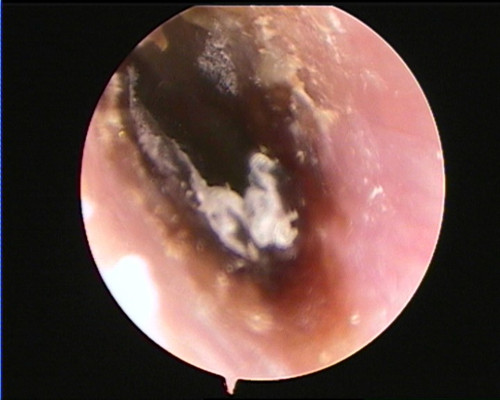

湖南省人民医院耳鼻咽喉头颈外科三病区主任王宁通过耳内镜检查发现,吴女士左侧外耳道充血肿胀,耳道表面和鼓膜上还布满了大量真菌菌丝,吴女士被诊断为真菌性外耳道炎。